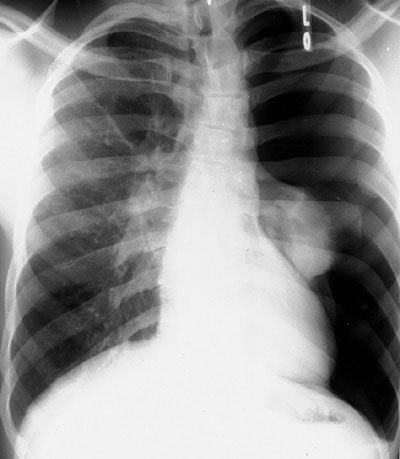

1 diagram

CHOOSE A DIAGRAM OF LING INFILTRATION

- 1

- 2

- both of them